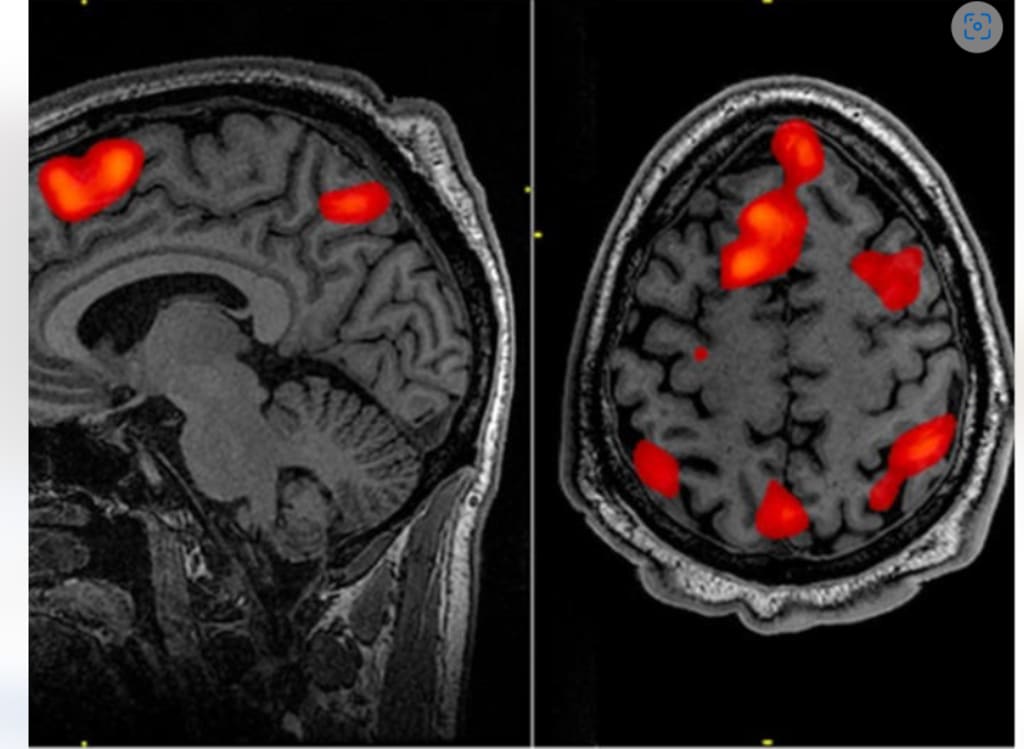

Fortunately, the Japanese research team managed to unravel the topic, as reported in a paper published in Nature Communications Online. With the state-ART approach previously developed by the team, they selectively switch themselves from various neuropaths that come from the OFC of monkeys in newly designed behavioural tasks, revealing independent features.

The team led by computed tomography, positron emisomography and magnetic resonance imaging was able to assess the effectiveness of local infusion drugs. By observing how the performance of monkeys changed, researchers were able to determine the functioning of these paths.

They found that the OFC path connecting to the caudate core is necessary for experience-based adaptation, and that knowledge-based coordination is important during the OFC path connected to the central thalamus.